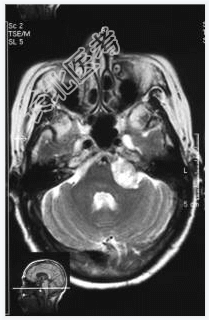

- [材料题] 患者,女性,71岁,因耳鸣、双下肢乏力4~5月,进行性发展入院。体检:左耳听力下降,行走碎步,四肢肌力Ⅴ级,肌张力略高。临床诊断:帕金森综合征。做头颅MRI检查。

- 简答题1、请问该病例诊断是什么?

- 简答题2、请问诊断依据是什么?

- 简答题3、请问鉴别诊断有哪些?

- 简答题4、左听神经鞘瘤的典型症状是什么,以及它是如何影响患者的听力和平衡功能的?

- 简答题5、左听神经鞘瘤治疗措施有哪些?